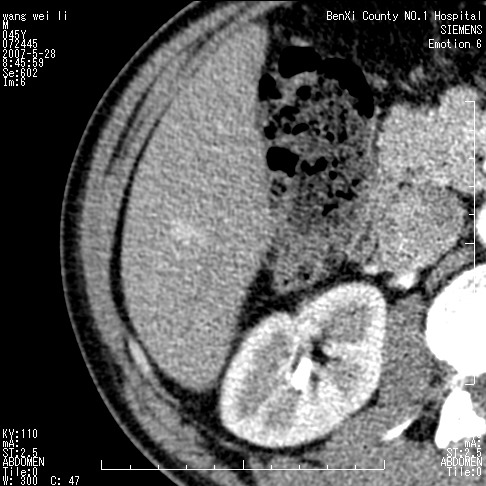

以下是引用还珠格格在2007-5-28 12:06:00的发言:[br]肝右叶后段病灶动脉期结节状强化,既然静脉期、延迟期为等密度充填 应考虑 肝右叶后段典型血管瘤。